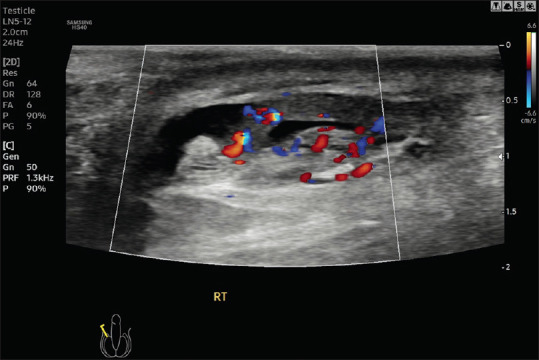

Acute Scrotal Pain - Role of Sonographic Evaluation in Solving Diagnostic Dilemma.